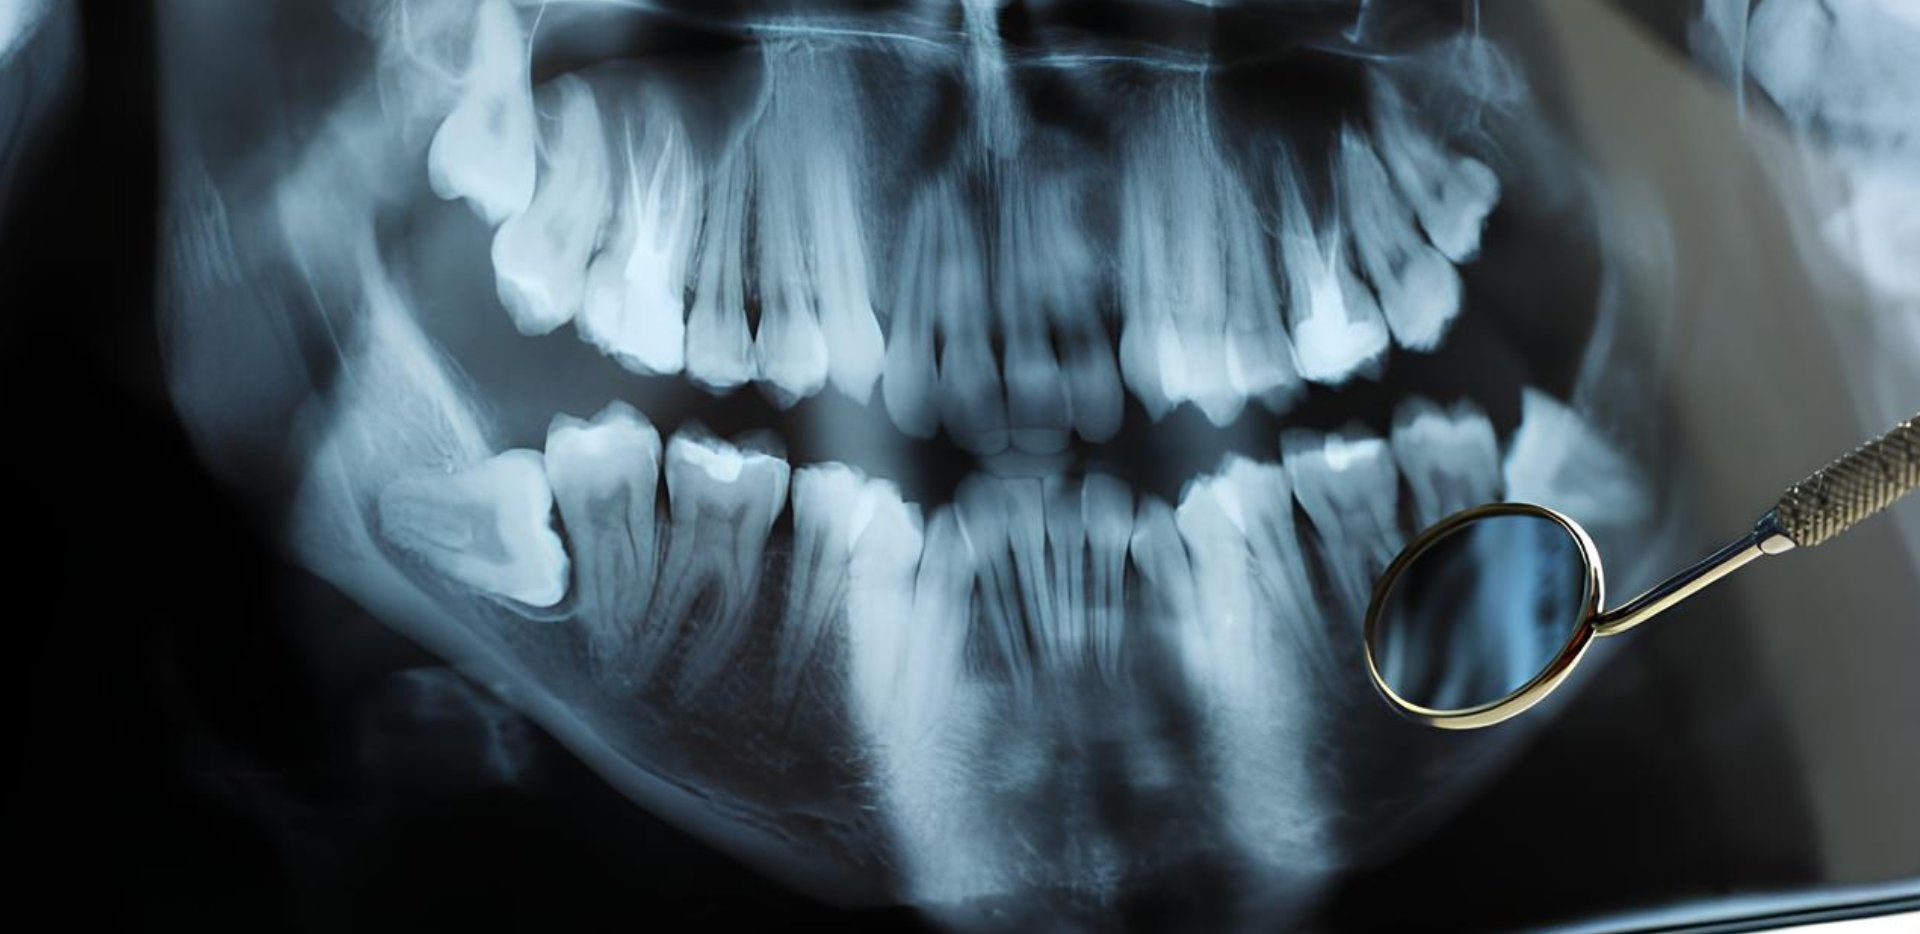

Il est assez simple d'extraire une dent totalement visible dans la bouche : cela implique une anesthésie avec un anesthésique local, puis après quelques manipulations autour de la gencive, la dent est extraite. Toutefois, ce n'est généralement pas le cas avec les dents de sagesse. Situées à l’arrière de la bouche, la plupart des dents de sagesse n’ont pas assez d’espace pour sortir correctement et sont considérées comme étant incluses. En fait, neuf personnes sur dix ont au moins une dent incluse, indique le Dr Patrick Rheault.

L'extraction des dents incluses requiert habituellement de retirer de l'os et du tissu gingival, ce qui en fait une intervention plus invasive que l'extraction de dents normalement positionnées. Et comme les quatre dents de sagesse sont généralement extraites en même temps, il est recommandé de consulter un stomatologue et d'avoir recours à un certain type de sédation au cours de l'intervention.